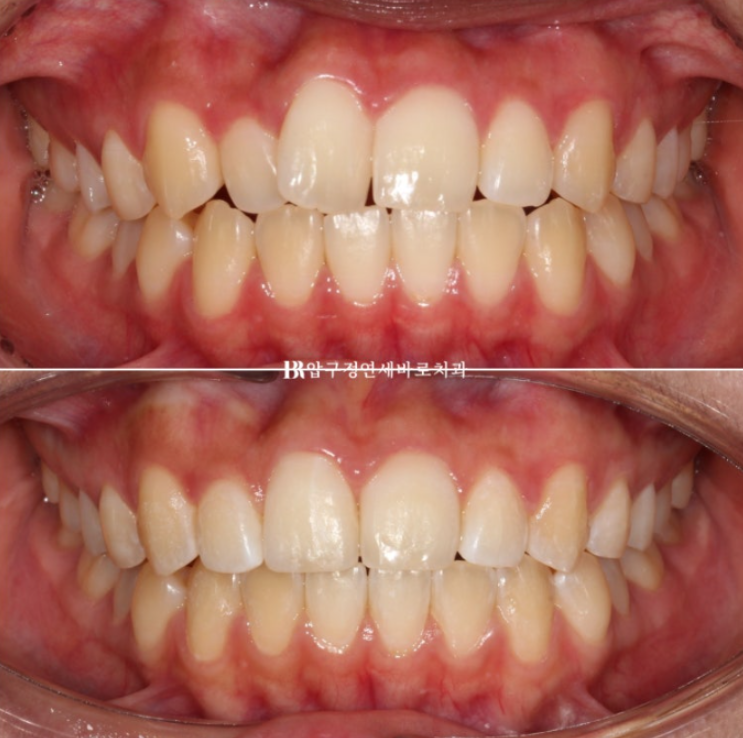

전 후 비교 보겠습니다.

토탈 치료 기간은 6개월 입니다.

23.12~24.06

심해보이는 덧니도 적절하게 치료하면 의외로 짧고 간단하게 교정이 마무리가 될 수 있습니다.